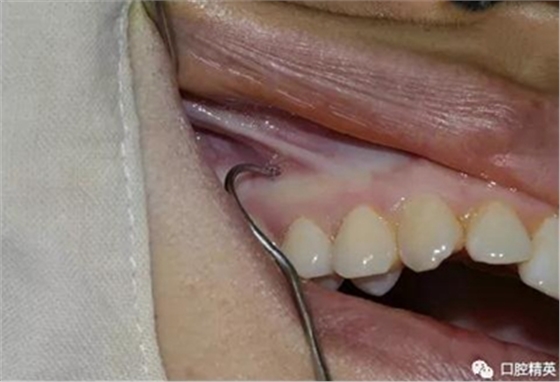

先使用刀背劃一垂直于頜骨矢狀平面的印記,以確定種植釘?shù)慕h(yuǎn)中位置。

常用11號尖刀片劃一個(gè)小切口,切開粘骨膜,牙科小挖匙分離粘骨膜。

再次,植入微型種植體,在附著牙齦處不需要粘骨膜翻瓣,在牙槽黏膜處則需要切開黏膜以避免植入時(shí)軟組織被卷入,植入部位通常在膜齦結(jié)合部位或偏根方2~3mm,植入角度與骨面垂直并傾斜15~20度,即向根尖方向植入,術(shù)后拍根尖片以確認(rèn)與牙根的關(guān)系。術(shù)后口服抗生素預(yù)防感染并進(jìn)行口腔衛(wèi)生宣教。